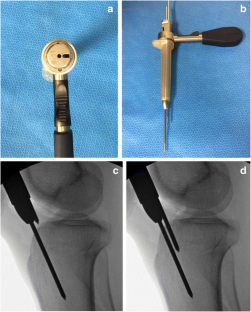

Fig. 2